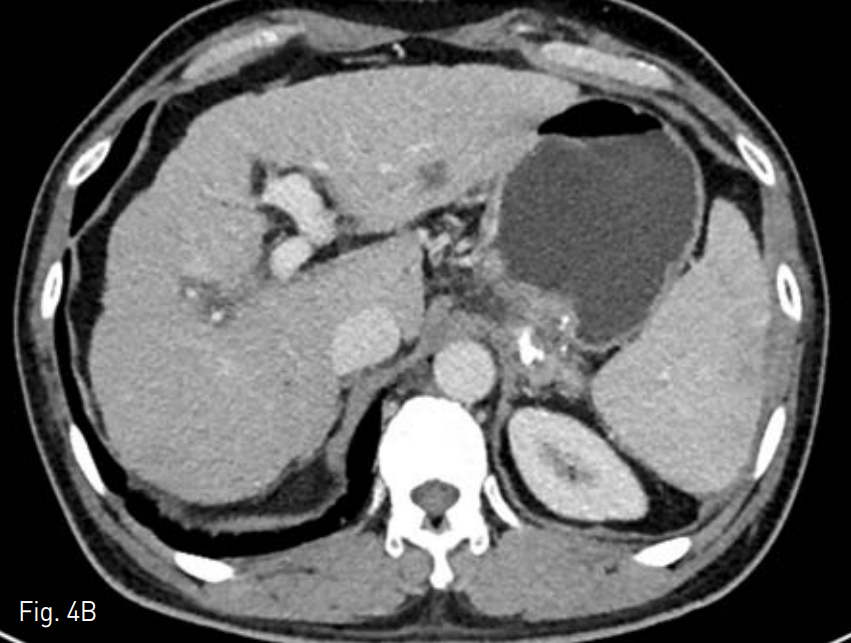

이후 발열은 관찰되지 않고 배액양이 5cc 이하로 감소하였으며 배액관을 통해 시행한 관조영술상 농양강이 허탈 되어 배액관을 제거하였다. 시술 1주일 후 촬영한 조영증강 전산화 단충촬영술에서 허탈된 농양강과 함께 비장에 경색으로 의심되는 쐐기 모양의 저음영의 영역이 관찰되었으나(Fig. 4A) 3개월 뒤 시행한 검사에서 저음영의 영역은 사라진 것을 관잘할 수 있었다(Fig. 4B).

A. Contrast enhanced CT scans obtained a week after the procedure shows decreased amount of abscess. Notice the wedge shaped low density lesion in the spleen, suggesting splenic infarction